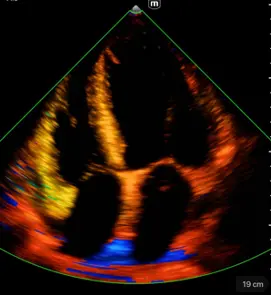

Различни режими на визуализация: B-mode, M-mode, Color Doppler, Power Doppler, PW Doppler

B-режим, М-режим, цветен доплер, Power доплер и PW доплер

Множество режими на визуализация

Бърза диагностика на сърдечната функция; скрининг за сърдечна патология

Клинични снимки